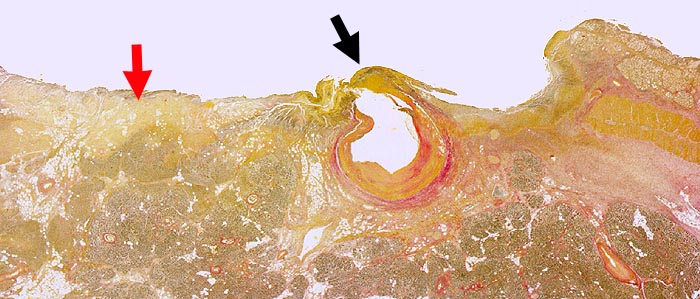

PathoPic ID 236 - Chronisches Ulkus duodeni: Arrosion A. pancreaticoduodenalis

Chronisches Ulkus duodeni: Arrosion A. pancreaticoduodenalis

Bis in das

►

Pankreas penetrierendes Duodenalulkus. Im Zentrum die

arrodierte Arteria pancreaticoduodenalis.

Tödliche Ulkusblutung bei Gefässarrosion. NSAR Medikation.